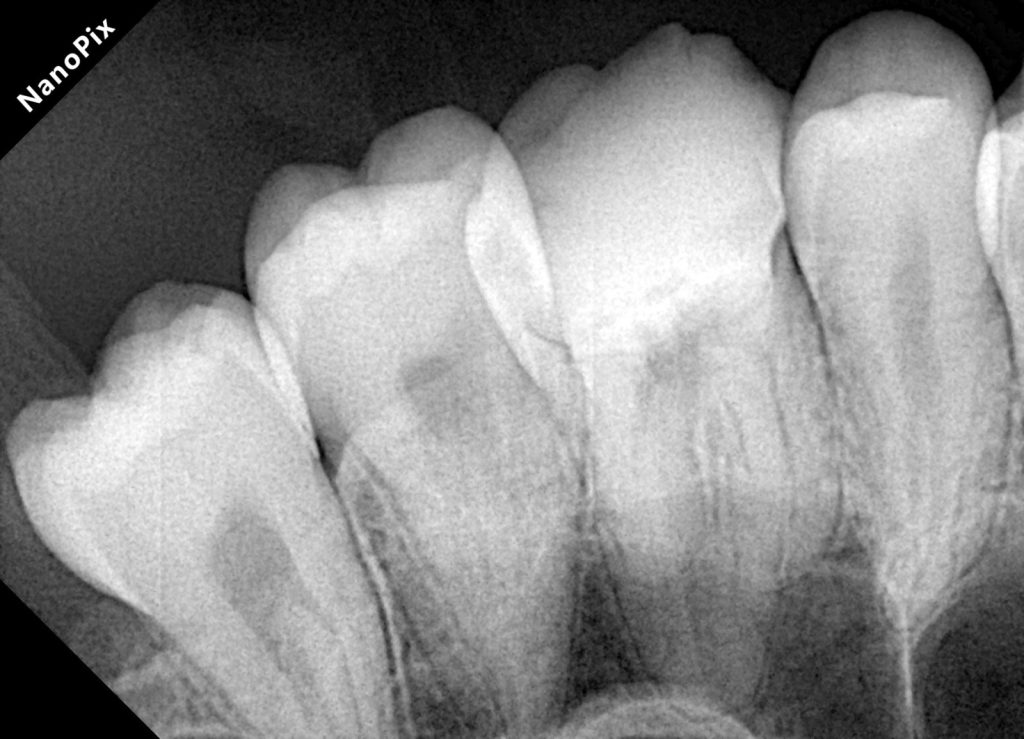

1. ENDODONTIC DIAGNOSIS & CLEANING UNDER MAGNIFICATION

2. CAVITY DESIGN & PREPARATION FOR RESTORATION

Pericervical Dentin Preservation

Only infected dentin was removed. This zone is critical for long-term fracture resistance.

Removal of Old Restorations & Caries

After cleaning, a deep proximal margin was revealed—subgingival and not suitable for direct composite.

This indicated the need for Deep Margin Elevation (DME) to bring the margin supragingival.